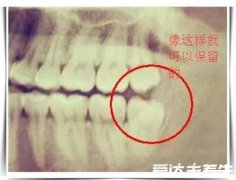

拔了智齿后悔终身,这是因为拔牙是有一定的后遗症的,但是有些情况下的智齿拔除之后好处要大于坏处,这种情况下还是需要拔牙,如果智齿没有对口腔中的其他牙齿或者是黏膜造成伤害,能够正常使用就不需要拔除,大家最好是听从医生的建议是否需要拔除智齿。